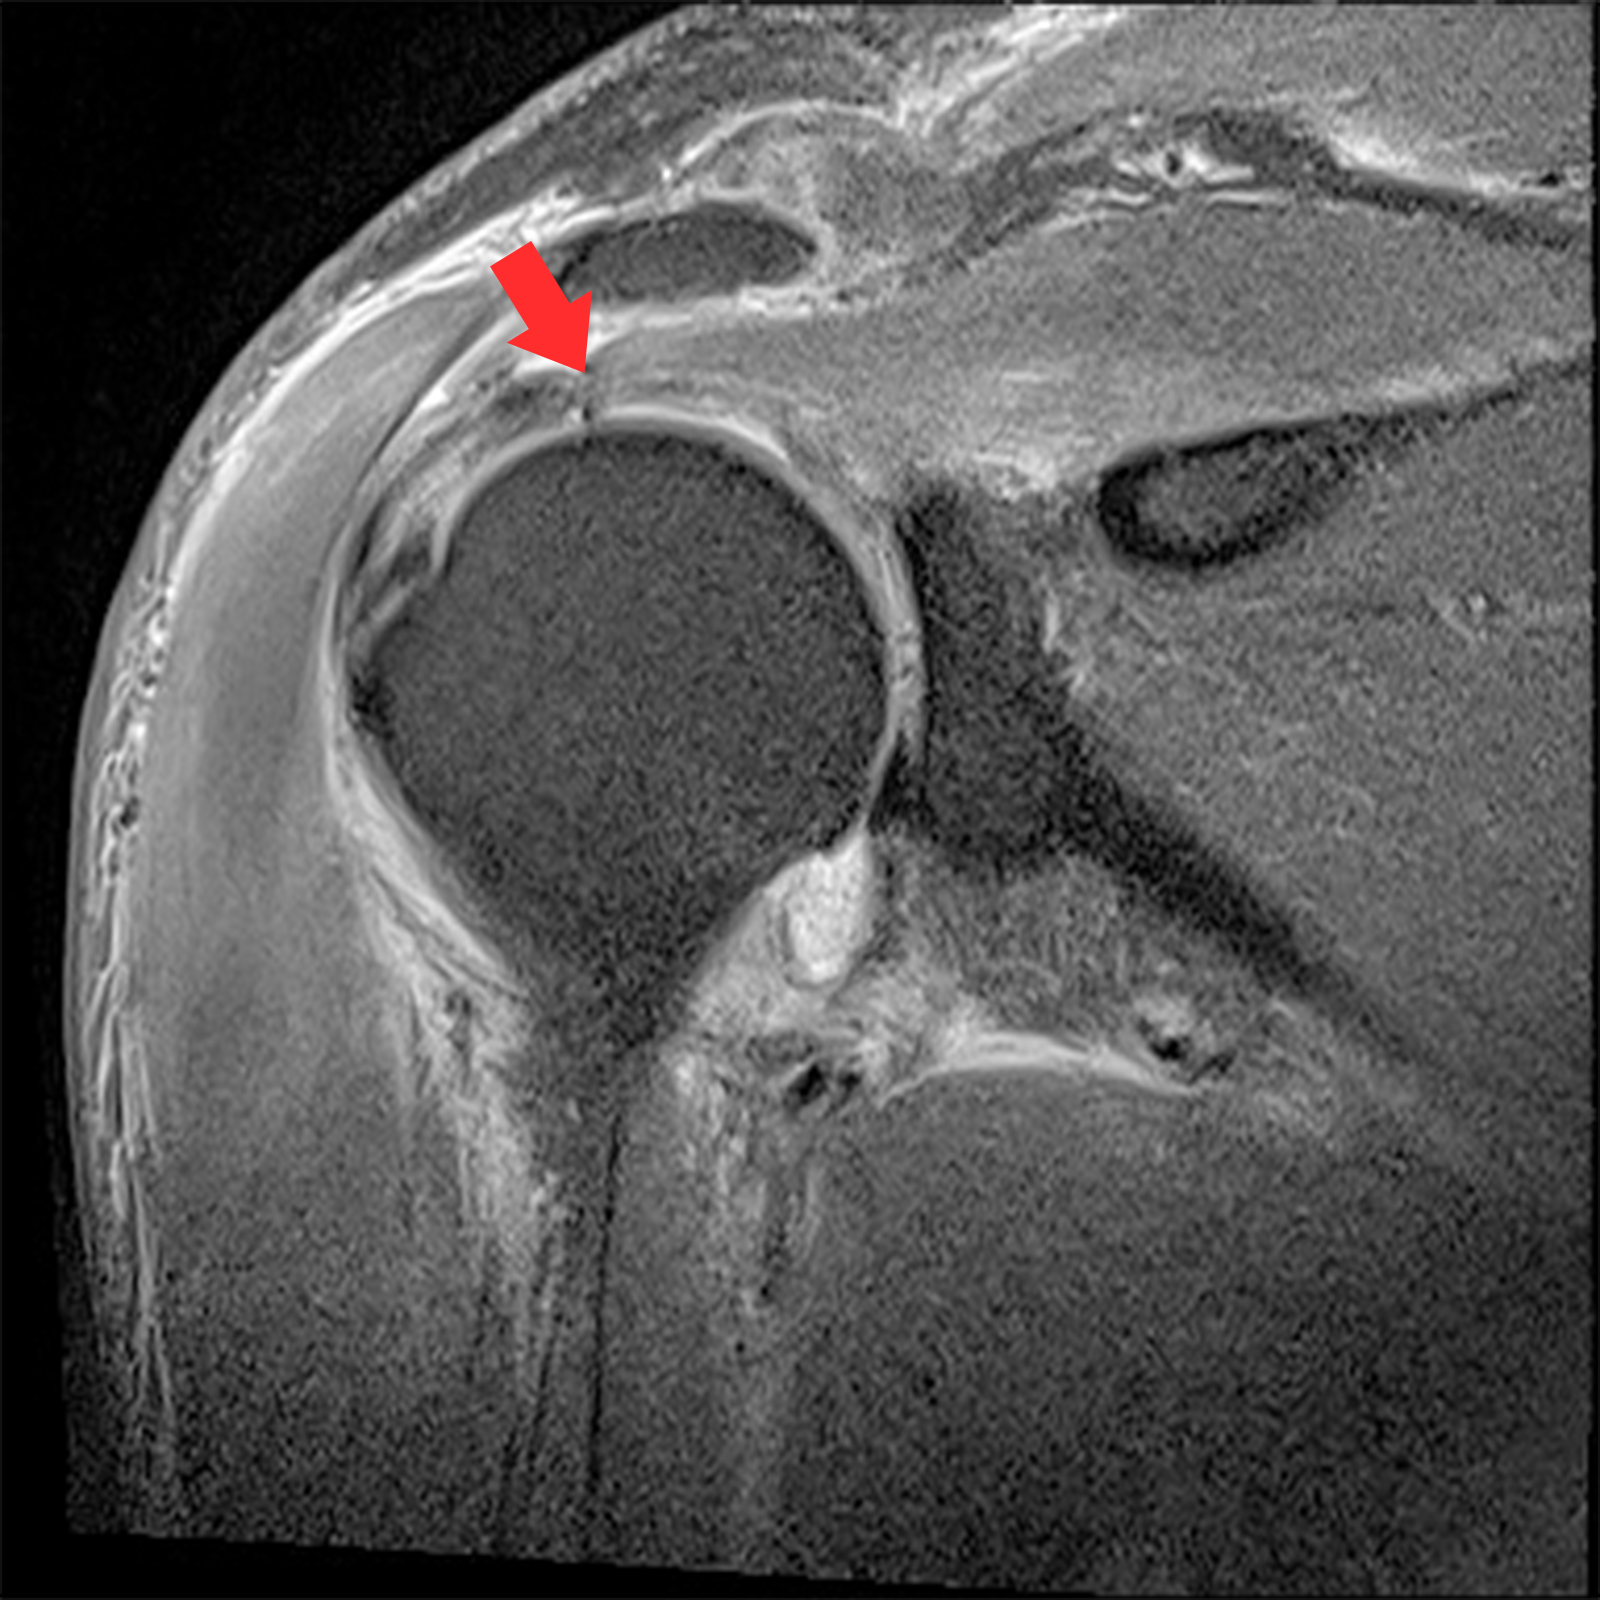

MRI 촬영시 정상적인 어깨의 경우 회전근개가 까맣게 나타나지만, 파열된 경우 하얗게 보여짐

관절내시경 수술 전

찢어지고 파열된 회전근개 모습

2022.06.15